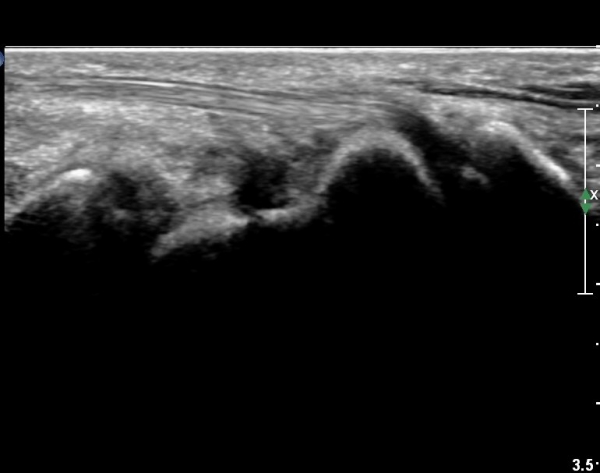

È®ÁøÀ» À§ÇÑ ÃÊÀ½ÆÄ°Ë»ç¿¡¼ ÁÖ»ó°ñ °ñÀý È®ÀÓ µÊ.

ÁÖÁöÇÏ´Ù½ÃÇÇ ÁÖ»ó°ñ °ñÀýÀº ´Ü¼ø¹æ»ç¼±°Ë»ç¿¡¼ È®ÀεÇÁö ¾Ê´Â °æ¿ì°¡ ÈçÇѵ¥

ÃÊÀ½ÆÄ°Ë»ç¸¦ ½ÃÇàÇÏ¸é ¹Ì¼¼ÇÑ °ñÀýµµ Áø´ÜÀÌ °¡´ÉÇÏ´Ù. |